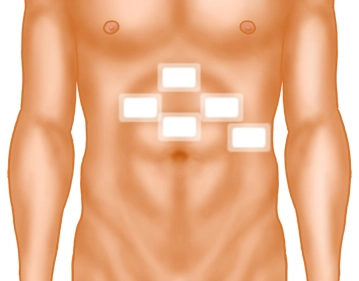

Ein kleiner Hautschnitt erfolgt deutlich oberhalb des Nabels in der Mittellinie. Nach Einführen der Verresnadel und Überprüfung der korrekten Lage wird das Pneumoperitoneum angelegt.

Trokarpositionierung